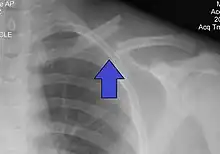

The basic method to check for a clavicle fracture is by an X-ray of the clavicle to determine the fracture type and extent of injury. In former times, X-rays were taken of both clavicle bones for comparison purposes. Due to the curved shape in a tilted plane X-rays are typically oriented with ~15° upwards facing tilt from the front. In more severe cases, a computerized tomography (CT) or magnetic resonance imaging (MRI) scan is taken. However, the standard method of diagnosis through ultrasound imaging performed in the emergency room may be equally accurate in children.[5]